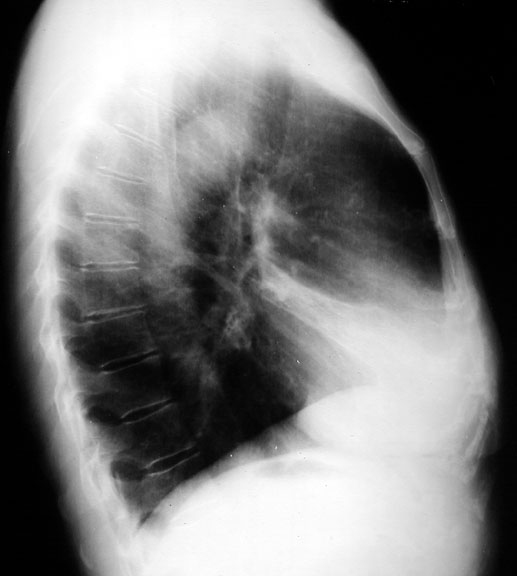

RML Atelectasis

• Vague density in right lower lung field, almost normal

• RML atelectasis in lateral view, not evident in PA view